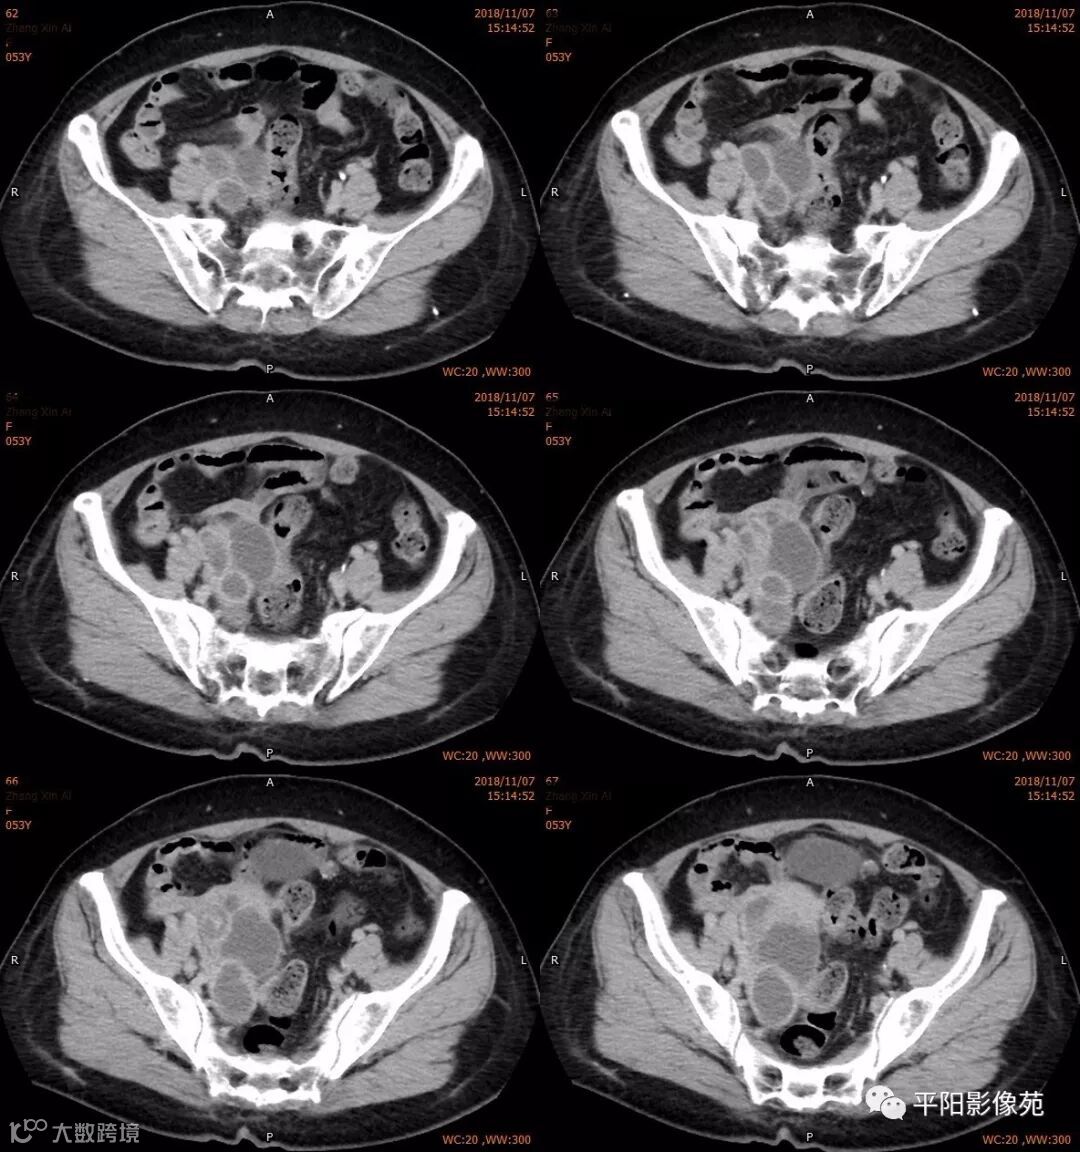

右附件区薄壁囊性病变,壁明显强化,边界不清,供血动脉源自子宫动脉,且局部动脉血管增多;其内侧可见卵圆形无强化囊性病灶。

附件区病变多见于卵巢,以囊性为主的病灶多为卵巢囊肿、粘液/浆液性囊腺瘤、皮样囊肿等,这些病灶都具有鲜明瘤体结构,且壁强化多为轻-中度,供血动脉多源自卵巢动脉;而本例患者右附件区薄壁囊性病灶,多位置观察形态为迂曲管状,且壁有明显延迟强化,供血动脉源自子宫动脉,较对侧血管丰富,故而考虑源自输卵管或子宫病变,但子宫发生的薄壁囊性病变较少,多见于子宫肌瘤囊变,完全囊变者少见,且形态轮廓与肌瘤相同为球形故而排除,结合患者腹痛前有感冒病史,且有压痛,因此考虑输卵管积脓可能。其内侧无强化囊性肿块,考虑卵巢囊肿可能。